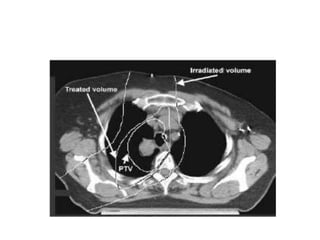

• As a result of treatment planning, volumes described.

– Treated volume (TV).

– Irradiated volume (IRV).